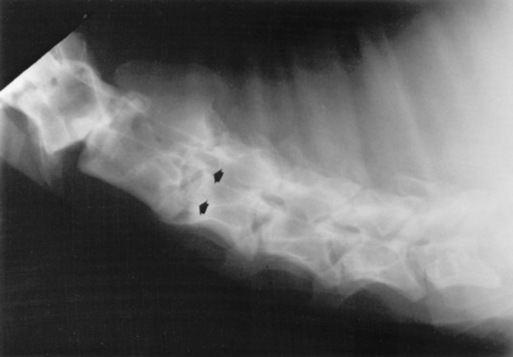

Survey radiographs of the cervical spine are obtained in standing, sedated horses. Cervical radiographs are evaluated by subjective assessment of vertebral malformation and objective determination of vertebral canal diameter.1878 The five categories of cervical malformation subjectively assessed in horses with CVSM are DJD of the articular processes, subluxation between adjacent vertebrae, flare of the caudal physis of the vertebral body, abnormal ossification patterns, and caudal extension of the dorsal laminae1878,1880 (Figs. 35-26 and 35-27). Although the presence of characteristic vertebral malformations supports the diagnosis of CVSM, subjective evaluation of survey radiographs does not reliably discriminate between horses affected and those unaffected by CVSM.1868,1878 DJD of the articular processes of the caudal cervical vertebrae is the most common and severe malformation observed in affected horses.1878 However, degenerative arthropathy occurs in 10% to 50% of nonataxic horses and is the most common and severe vertebral malformation in horses without CVSM.1869,1878 Subjective evaluation of degenerative arthropathy of the articular processes may lead to a false-positive diagnosis of CVSM.1868

Fig. 35-27 Survey radiograph of fifth and sixth cervical vertebrae. Degenerative joint disease, bony proliferation, and a facet fracture (arrows) can be seen on the articular processes of the C5-C6 articulation.